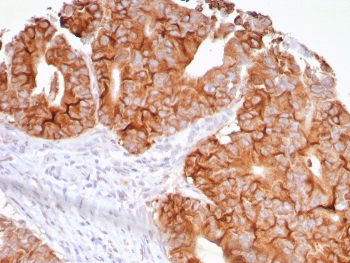

Immunohistochemistry of TNFSF15 antibody in human colon tissue. FFPE human colon shows membranous and cytoplasmic HRP-DAB brown staining within glandular epithelial cells, consistent with VEGI expression in vascular and epithelial compartments. Clone VEGI/7799R was used as a recombinant rabbit monoclonal antibody for detection. Heat-induced epitope retrieval was performed by boiling tissue sections in pH 9, 10 mM Tris with 1 mM EDTA for 20 minutes followed by cooling prior to staining.